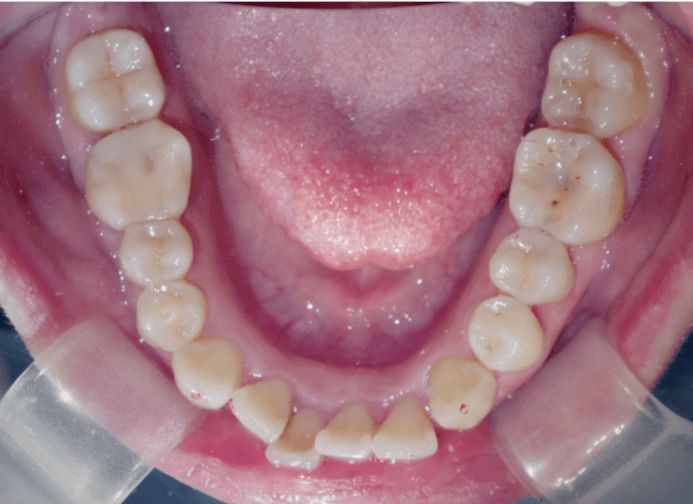

八重歯(叢生)

BEFORE

AFTER

担当医コメント

八重歯を並べるためのスペースを上顎大臼歯の遠心移動とIPRで確保する計画を立て、インビザラインで治療することとした。

年齢/性別

26歳 男性

主訴

八重歯が気になる

リスク

歯肉退縮が起こる可能性がある

費用

85万円(矯正費用)

期間

1 5 ヶ月